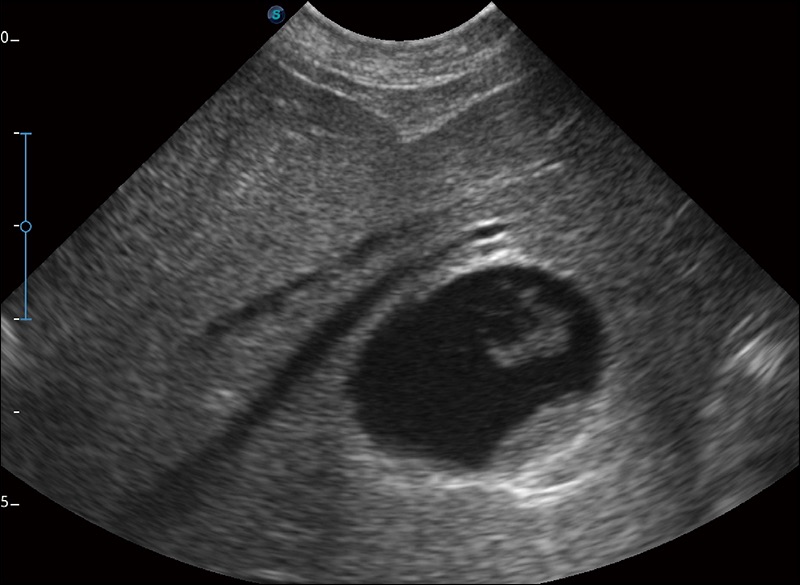

扩展成像

支持线阵和凸阵探头,一键操作即可获得更宽的图像视野